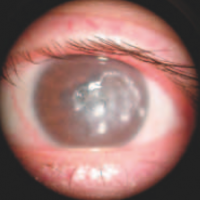

Ectasie cornéenne